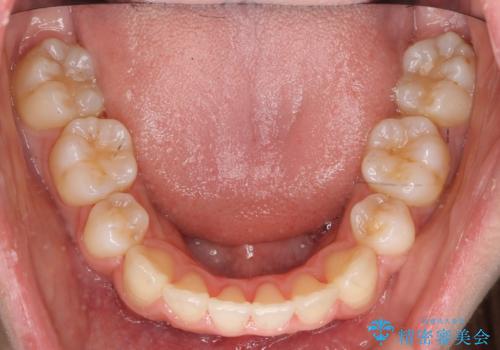

- 前歯のがたがたを主訴に来院。

八重歯と、前歯のやや開咬の症状もあり難易度としては中等度でした。

上下左右の小臼歯を抜歯し、ワイヤー矯正を行いました。

犬歯のコントロールが難しく、矯正用ミニスクリューを併用しました。